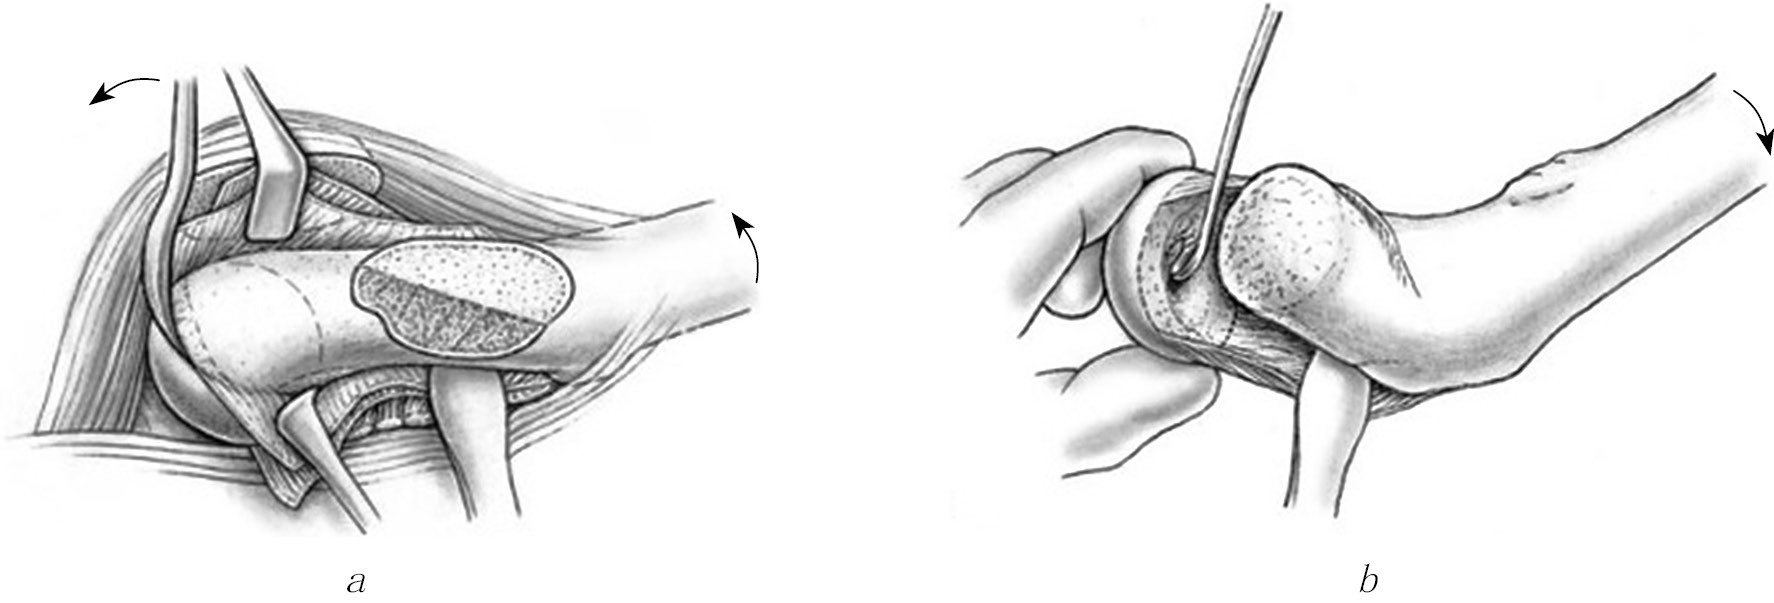

The most detailed description of the modified Dunn surgery technique, in our opinion, was given by Ziebarth et al. in 2009 [19]. In our work, we strove for strict adherence to the author’s technique, including all the described details of the intervention. Particular attention was paid to determining the direction and length of the joint capsule dissection (Z-shaped during surgery on the right and anti-Z-shaped during surgery on the left joint) (Fig. 1, a) and careful subperiosteal isolation of the femoral neck, allowing us to obtain a massive graft nourishing the epiphysis (Fig. 1, b). In addition, in order to avoid damage to the formed nourishing graft containing ascending branches of a. circumflexa femoris medialis, it is necessary to be extremely careful when performing a neck osteotomy (Fig. 2, a) and removal of the subepiphyseal trabecular bone with the remains of the growth plate (Fig. 2, b). To determine the presence and intensity of blood flow in the epiphysis, immediately after dislocation of the femoral head from the joint cavity, a hole in its anterior pole was drilled with a Kirschner wire. The absence of bleeding from the hole after osteosynthesis of the epiphysis and metaphysis indicated excessive tension of the nourishing graft; therefore, it was necessary to perform additional shortening of the neck. Depending on the severity of regional osteoporosis, two or three wires with a diameter of 2.5 mm were used to fix the epiphysis with bent threads on the end, which were brought into different planes from the side of the epiphysis (from the fovea capitis ossis femoris) and metaphysis.

Fig. 1. Technique of the modified Dunn surgery: a — Z-shaped section of the joint capsule; b — subperiosteal femoral neck isolation [19]